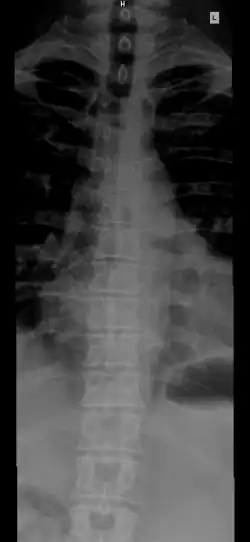

The spinal column, also known as the vertebral column, spine or backbone, is the core part of the axial skeleton in vertebrates. The vertebral column is the defining and eponymous characteristic of the vertebrate. The spinal column is a segmented column of vertebrae that surrounds and protects the spinal cord. The vertebrae are separated by intervertebral discs in a series of cartilaginous joints.[1] The dorsal portion of the spinal column houses the spinal canal, an elongated cavity formed by the alignment of the vertebral neural arches that encloses and protects the spinal cord, with spinal nerves exiting via the intervertebral foramina to innervate each body segment.

The number of vertebrae in a region can vary but overall the number remains the same. In a human spinal column, there are normally 33 vertebrae.[3] The upper 24 pre-sacral vertebrae are articulating and separated from each other by intervertebral discs, and the lower nine are fused in adults, five in the sacrum and four in the coccyx, or tailbone. The articulating vertebrae are named according to their region of the spine.

From top to bottom, there are 7 cervical vertebrae, 12 thoracic vertebrae and 5 lumbar vertebrae. The number of those in the cervical region, however, is only rarely changed,[4] while that in the coccygeal region varies most.[5] Excluding rare deviations, the total number of vertebrae ranges from 32 to 35.[6] In about 10% of people, both the total number of pre-sacral vertebrae and the number of vertebrae in individual parts of the spine can vary.[7][8][9] The most frequent deviations are: 11 (rarely 13) thoracic vertebrae, 4 or 6 lumbar vertebrae, 3 or 5 coccygeal vertebrae (rarely up to 7).[9]

The vertebrae in the human vertebral column is divided into different body regions, which correspond to the curvatures of the vertebral column. The articulating vertebrae are named according to their region of the spine. Vertebrae in these regions are essentially alike, with minor variation. These regions are called the cervical spine, thoracic spine, lumbar spine, sacrum, and coccyx. There are seven cervical vertebrae, twelve thoracic vertebrae, and five lumbar vertebrae.

From top to bottom, the vertebrae are:

- Cervical spine (neck): 7 vertebrae (C1–C7)

- Thoracic spine (chest/upper back): 12 vertebrae (T1–T12)

- Lumbar spine (lower back): 5 vertebrae (L1–L5)

- Sacrum (pelvis region): 5 (fused) vertebrae (S1–S5)

- Coccyx (tailbone): 4 (3–5, fused) vertebrae